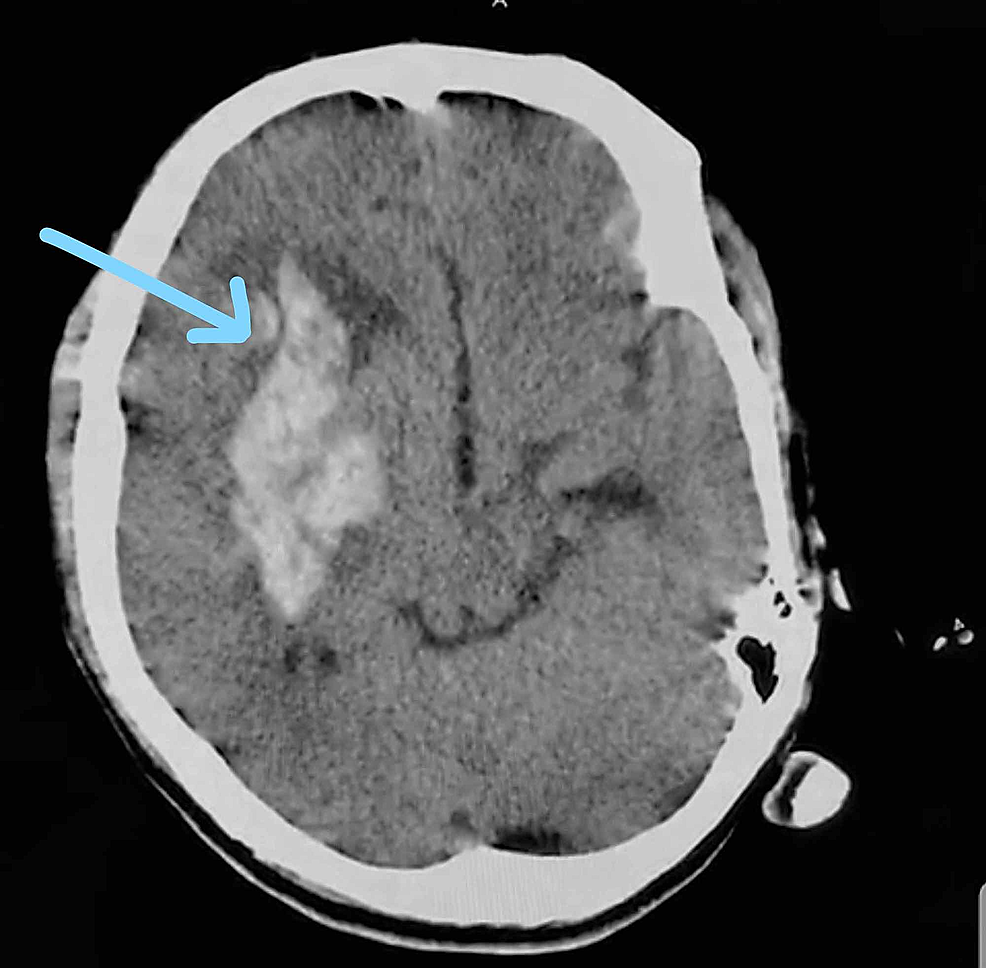

Initial CT scan showing the region of the bleed. Download Scientific Ct Scan Brain Bleed  Identifying the different types of intracranial haemorrhage.   intracranial haemorrhages are diagnosed via a ct head scan.   intracranial hemorrhage comprises 4 broad types of hemorrhage, including epidural hemorrhage, subdural hemorrhage,. Identifying a unilateral hemorrhage within the brain on a computed tomography (ct) scan is not.   ct scan is almost always the first imaging modality used to assess patients. Ct Scan Brain Bleed.